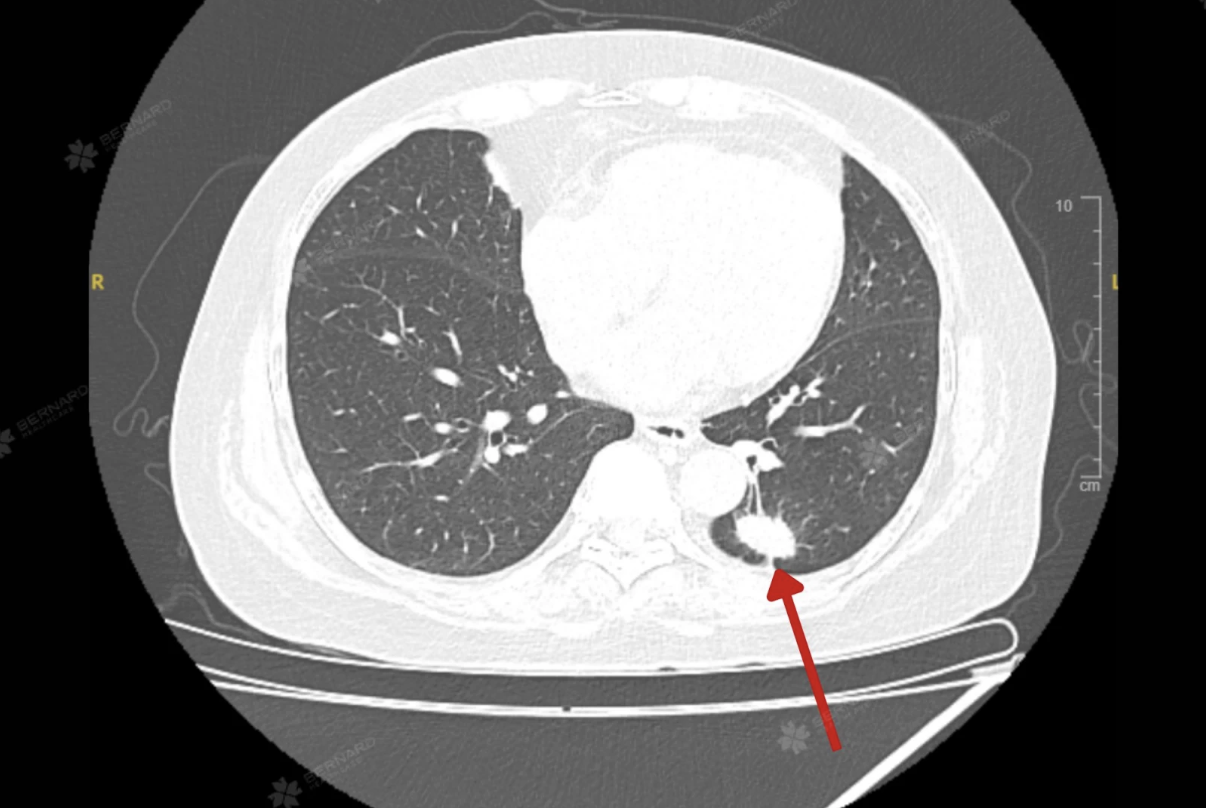

Kết quả CT Scan của bà K. cho thấy tổn thương choán chỗ thùy dưới phổi trái (S10), kích thước khoảng 1,5 x 2,5 cm, đậm độ mô, bờ tua gai và có co kéo mô phổi xung quanh. Những đặc điểm này gợi ý u phổi ác tính, cần kết hợp sinh thiết để xác định chính xác bản chất tổn thương.

Đáng chú ý, CT Scan còn ghi nhận một số hạch trung thất nghi di căn, với hạch lớn nhất thuộc nhóm 2, cùng các nốt nhỏ quanh rãnh liên thùy bé phổi phải (đường kính khoảng 3 mm) và nốt dưới màng phổi thùy lưỡi (đường kính khoảng 7 mm).

Đây có thể là dấu hiệu cho thấy tổn thương đã bước vào giai đoạn di căn hạch trung thất, tuy nhiên chưa ghi nhận bằng chứng lan rộng đến các cơ quan xa.